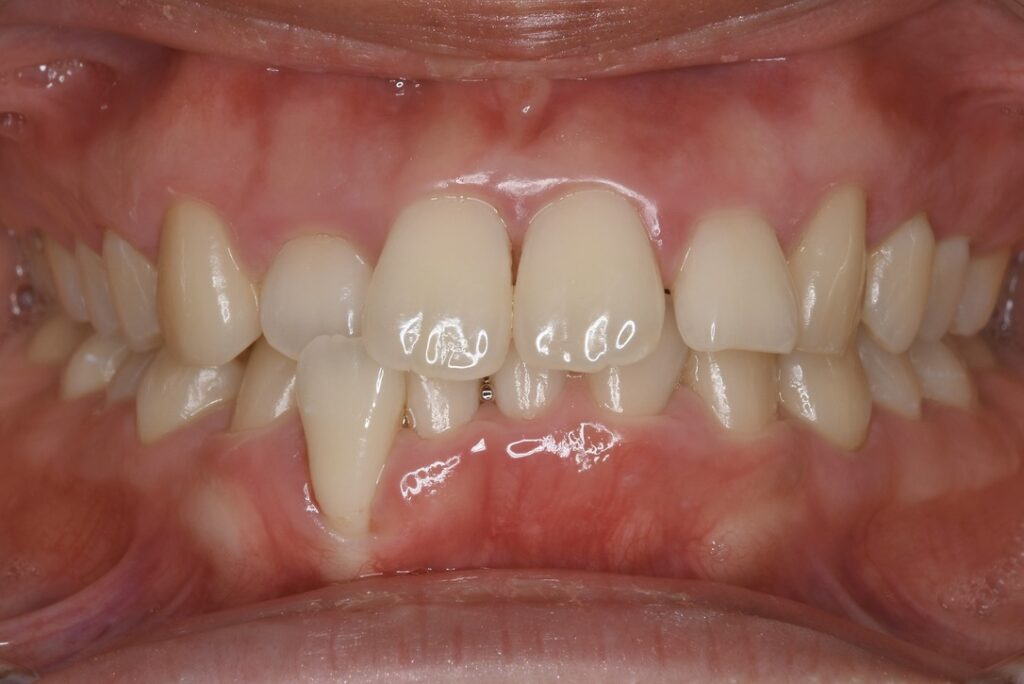

21歳 女性 治療期間:1年1ヶ月

叢生(ガタガタ)

マウスピース矯正装置(インビザライン)

BEFORE

主訴

周りの人の歯並びが綺麗で自分の歯並びを治したくなってきた。

診断名・主な症状

叢生

治療内容

上下とも歯並びの横幅を広げながら、でこぼこを解消しました。

マウスピース矯正(インビザライン)

抜歯あり(智歯抜歯)

1年1ヶ月

10回

85万円程度(税別)

リスク・副作用

痛み、歯肉退縮、歯根吸収、抜歯に伴う出血や腫れが生じることがあります。